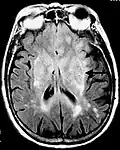

Axial fluid-attenuated inversion recovery MRI image demonstrating tumor-related infiltration involving both temporal lobes (Short arrow), and the substantia nigra (Long arrow).